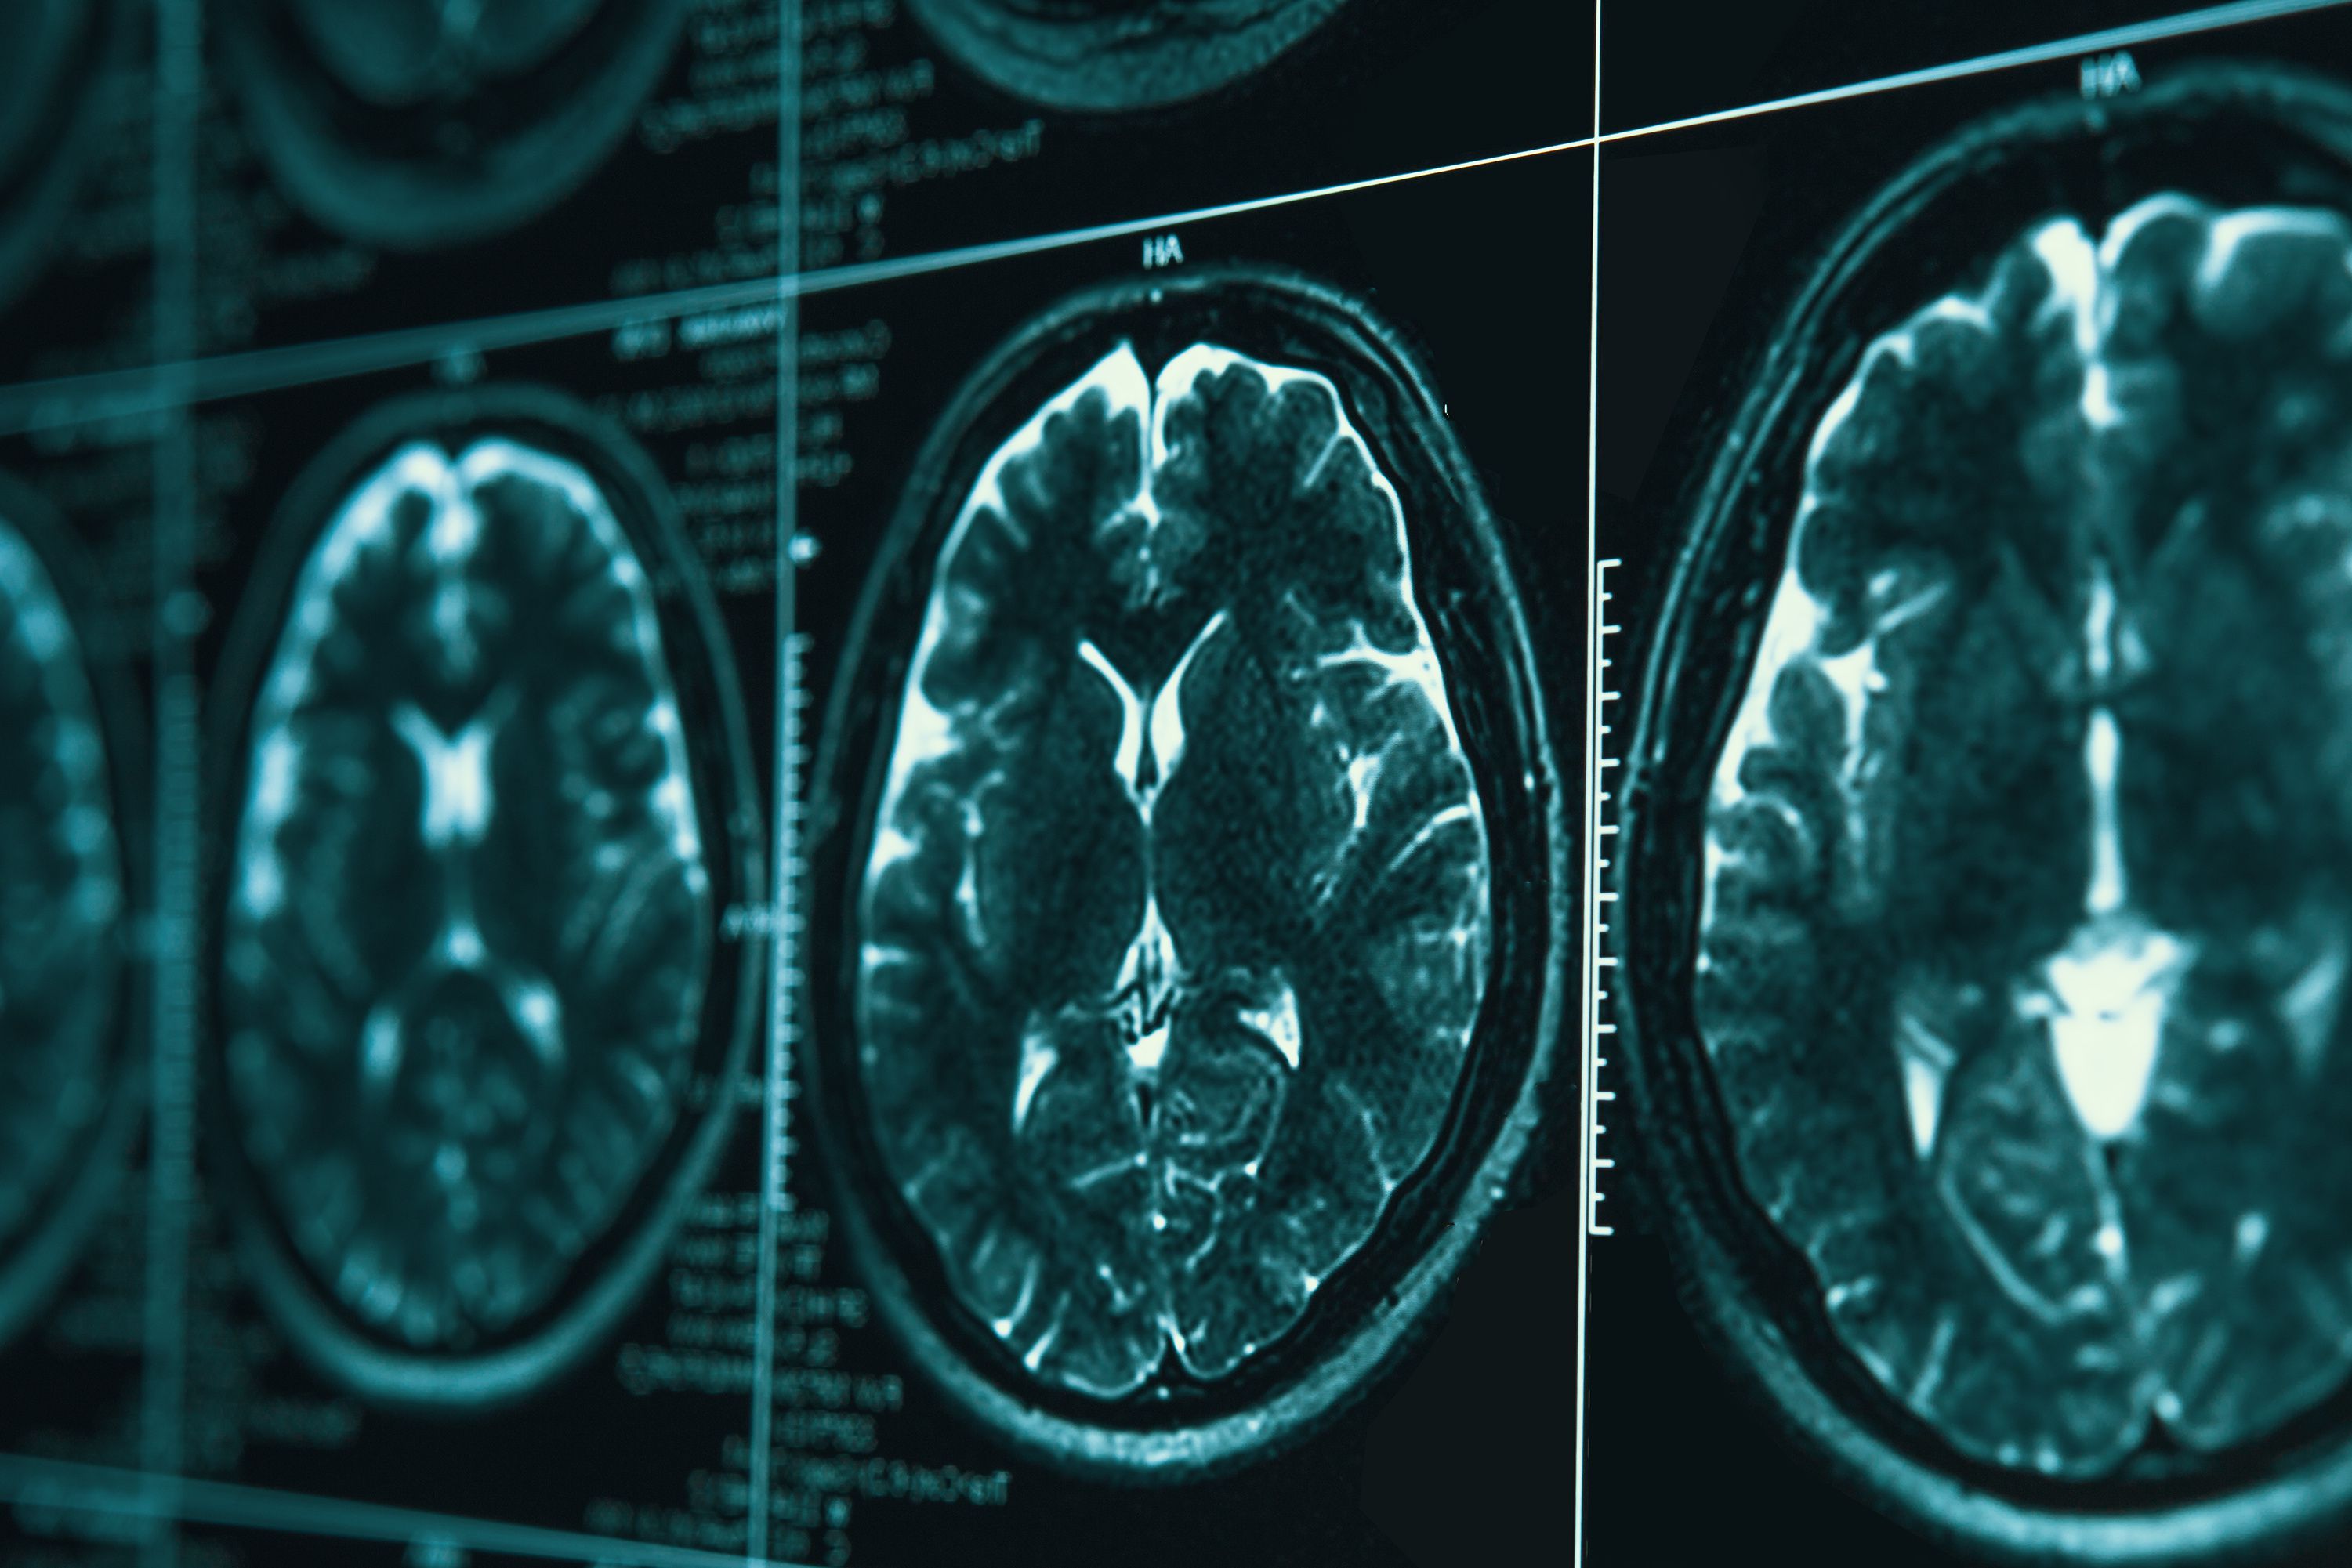

SALT LAKE CITY — Add this to the list of potential targets to treat Alzheimer's and other neurodegenerative disorders: Researchers in South Korea have discovered a network of lymphatic vessels at the back of the nose that help drain cerebral spinal fluid from the brain.

In other words, the drainage clears toxins from the brain. In a news release from the Institute for Basic Science, where the study originated, researchers note that "accumulation of waste in the brain, if not properly expelled, can damage nerve cells leading to impaired cognitive function, dementia and other neurodegenerative brain disorders. Hence, the regulation of (cerebrospinal fluid) production, circulation and drainage has long been a focus of scientific attention, especially in relation to age-related conditions like Alzheimer's disease and other neurodegenerative disorders."